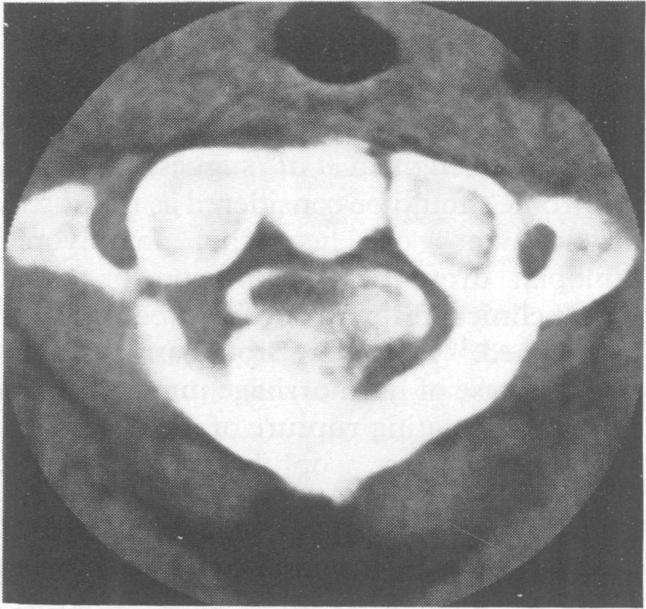

Syringomyelia associated with a spinal schwannoma: a case report.

J Neurol Neurosurg Psychiatry. 1990 May;53(5):438-9. doi: 10.1136/jnnp.53.5.438.